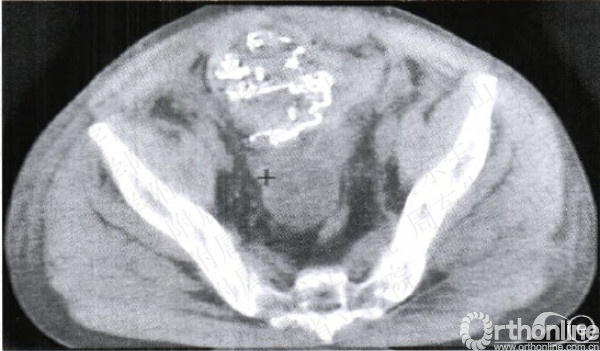

图l纱布填塞术止血手术及示意图a竹Z}Ir位x线片示Tile分型的B型骨盆骨折b急诊行纱布填塞术进行止血c示意图示取腹部正中切ICl(也可取耻骨上横切口和髂腹股沟切口),牵开腹膜,在腹膜外进行填塞d示意图示纱布填塞的位置:耻骨后方、髂窝及骨盆环与腹膜之间的腹膜外间隙e填塞术后行CT检查示纱布填塞于耻骨后方

对于剖腹探查患者,直接于剖腹探查切口进行填塞,填塞物直接压迫髂内动脉分支与骶前静脉丛(图1a一1c)。对于非剖腹探查患者,根据骨折类型判断出血部位,前环损伤出血则在耻骨联合上方约2cm处做一长约8em的横切口,将填塞物置于耻骨后方进行压迫止血。而对于后环损伤导致的出血则取髂腹股沟切口,逐层分离两侧腹膜外间隙至两侧骶髂关节前方,注意保持腹膜完整。将填塞物(无菌纱布或绷带)于腹膜外间隙,置于骶前、骶髂关节直至耻骨后方(图1d,1e)。填塞物直接压迫髂内动脉分支与骶前静脉丛。对侧同样进行填塞。填塞完毕后,连续缝合法逐层关闭皮下组织与皮肤。